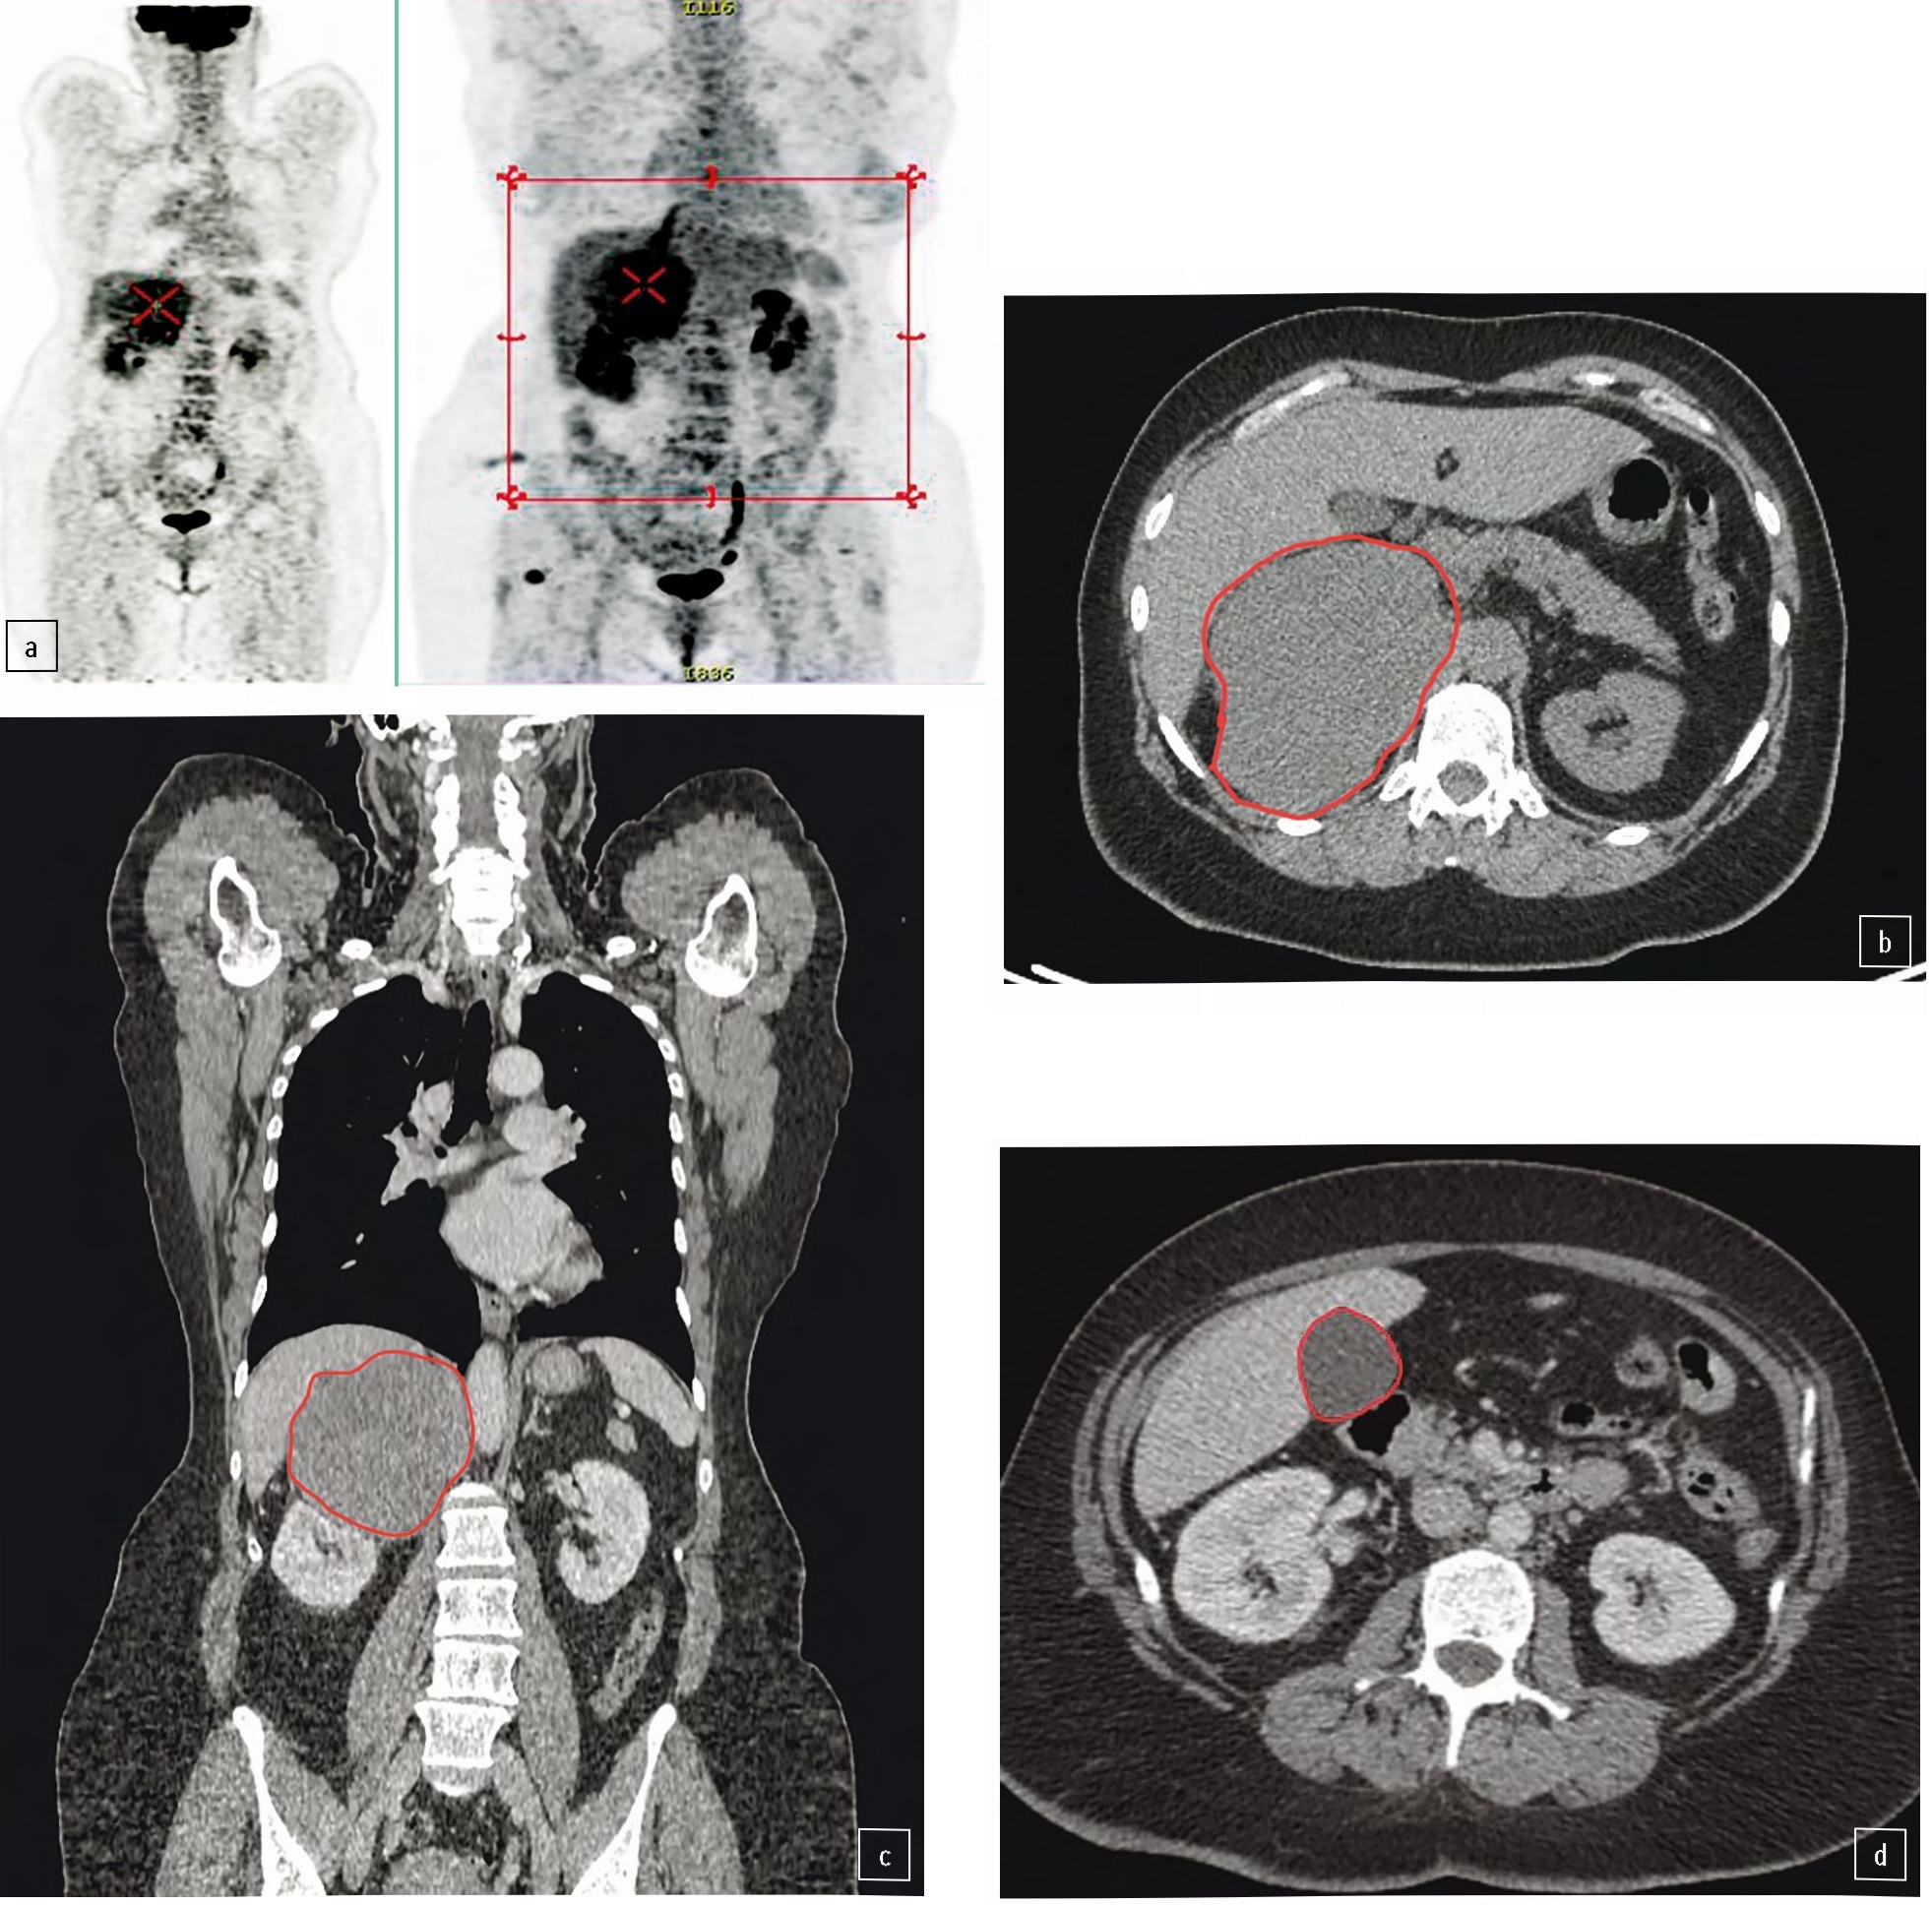

При контрольном обследовании в октябре 2021 г. выявлены образования в правой почке и левом надпочечнике (рис. 2).

Рис. 2. КТ органов брюшной полости от 10.2021: а – образование средней трети почки 30×28,5 мм; b – образование левого надпочечника 28×25 мм.

Fig. 2. Abdominal CT scan dated October 2021: a – a mass in the middle third of the kidney of 30×28.5 mm; b – left adrenal gland mass of 28×25 mm.

С учетом прогрессирования заболевания и наличия экспрессии опухолью рецепторов к соматостатину принято решение добавить к уже проводимой терапии митотаном пролонгированную форму аналога соматостатина – октреотид Депо/лонг в дозе 40 мг внутримышечно 1 раз в 28 дней.